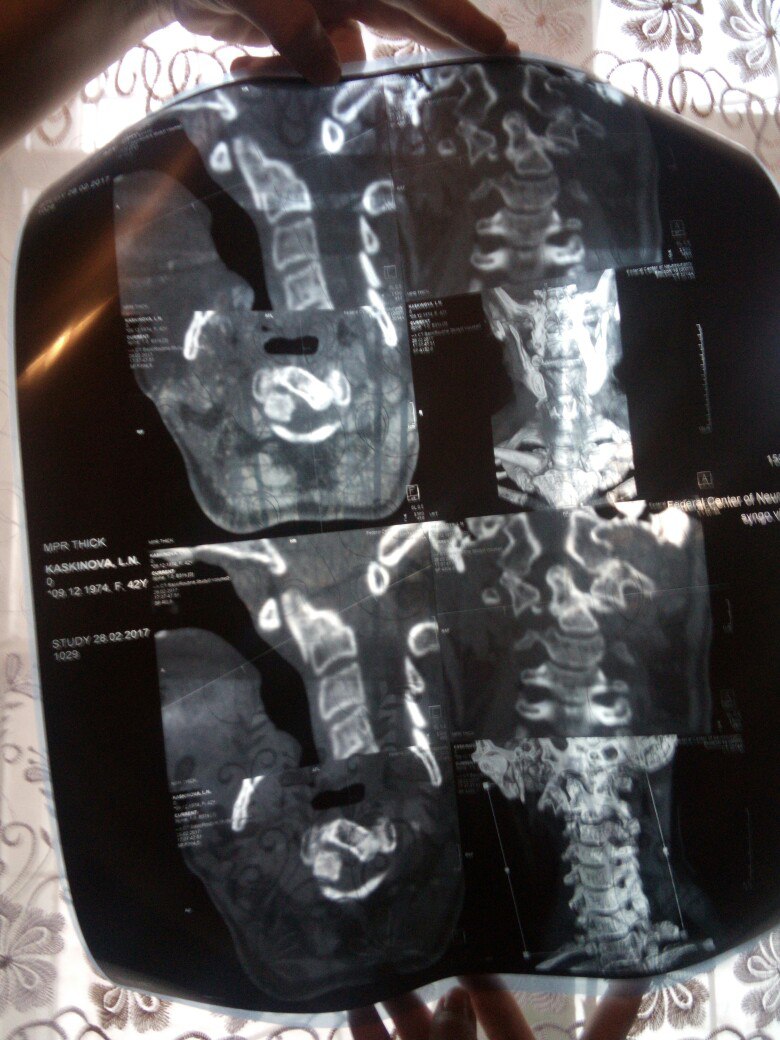

Здравствуйте Елена Васильевна .Я 9октября попала в ДТП у меня переломС2 позвонка с деформацией и вентральным смещением фрагмента.Цервикалгия.Я обращалась в г.Уфа,в г.Тюмень центр нейрохирургии,в г. Москва клиника ОртоСпайн ,мне везде отказали в оперативном лечении.Я хотела бы узнать ,какое лечение мне поможет,чтобы мне было легче.